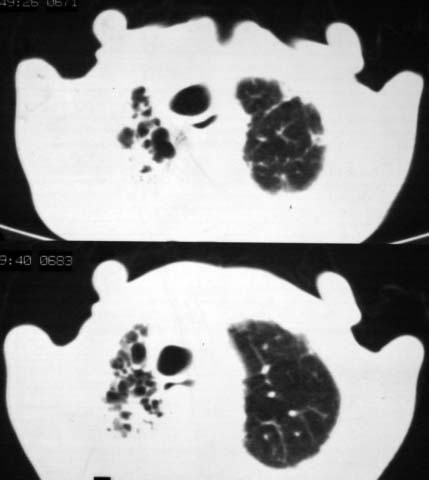

男,85岁,发热2月, 血常规:hgb99g/l.rbc2.55×1012/l.wbc3.8×109/l.n78.2%  l20.7% m1.1%.  hct26.3% .血沉20mm/hg.痰检结核杆菌阴性。ddp阳性。痰少粘稠色白。无咳血。

1.右上肺陈旧性肺结核灶;

2.左上肺、双下肺及右中叶肺炎(左上肺肺炎治疗后好转)

双肺结核

右上肺陈旧性肺结核灶,双肺感染灶〔大部份纤维化〕,肺气肿.

两肺陈旧性tb

双肺继发型结核

双肺继发型肺结核,肺纤维化,肺气肿,胸膜肥厚黏连。